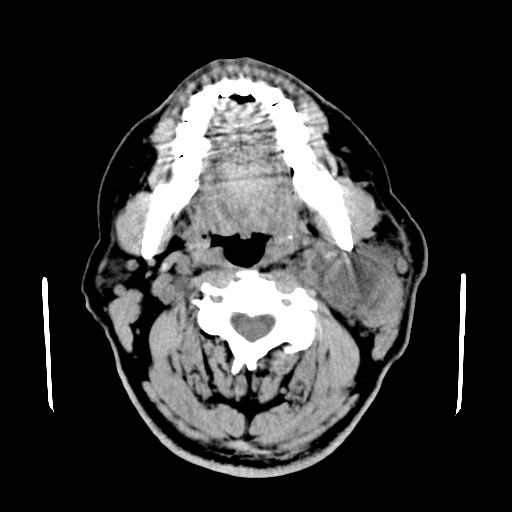

以下是引用卜一在2007-8-6 21:23:00的发言:[br]定位:左侧胸锁乳突肌内侧 颌下腺下后方。特征:弥漫性生长 软组织密度肿块,界限不清,内隐约见低密度坏死。考虑:神经源性肿瘤或血管源性肿瘤。

以下是引用wangzhanshuang在2007-8-6 21:08:00的发言:[br]腮腺混合瘤